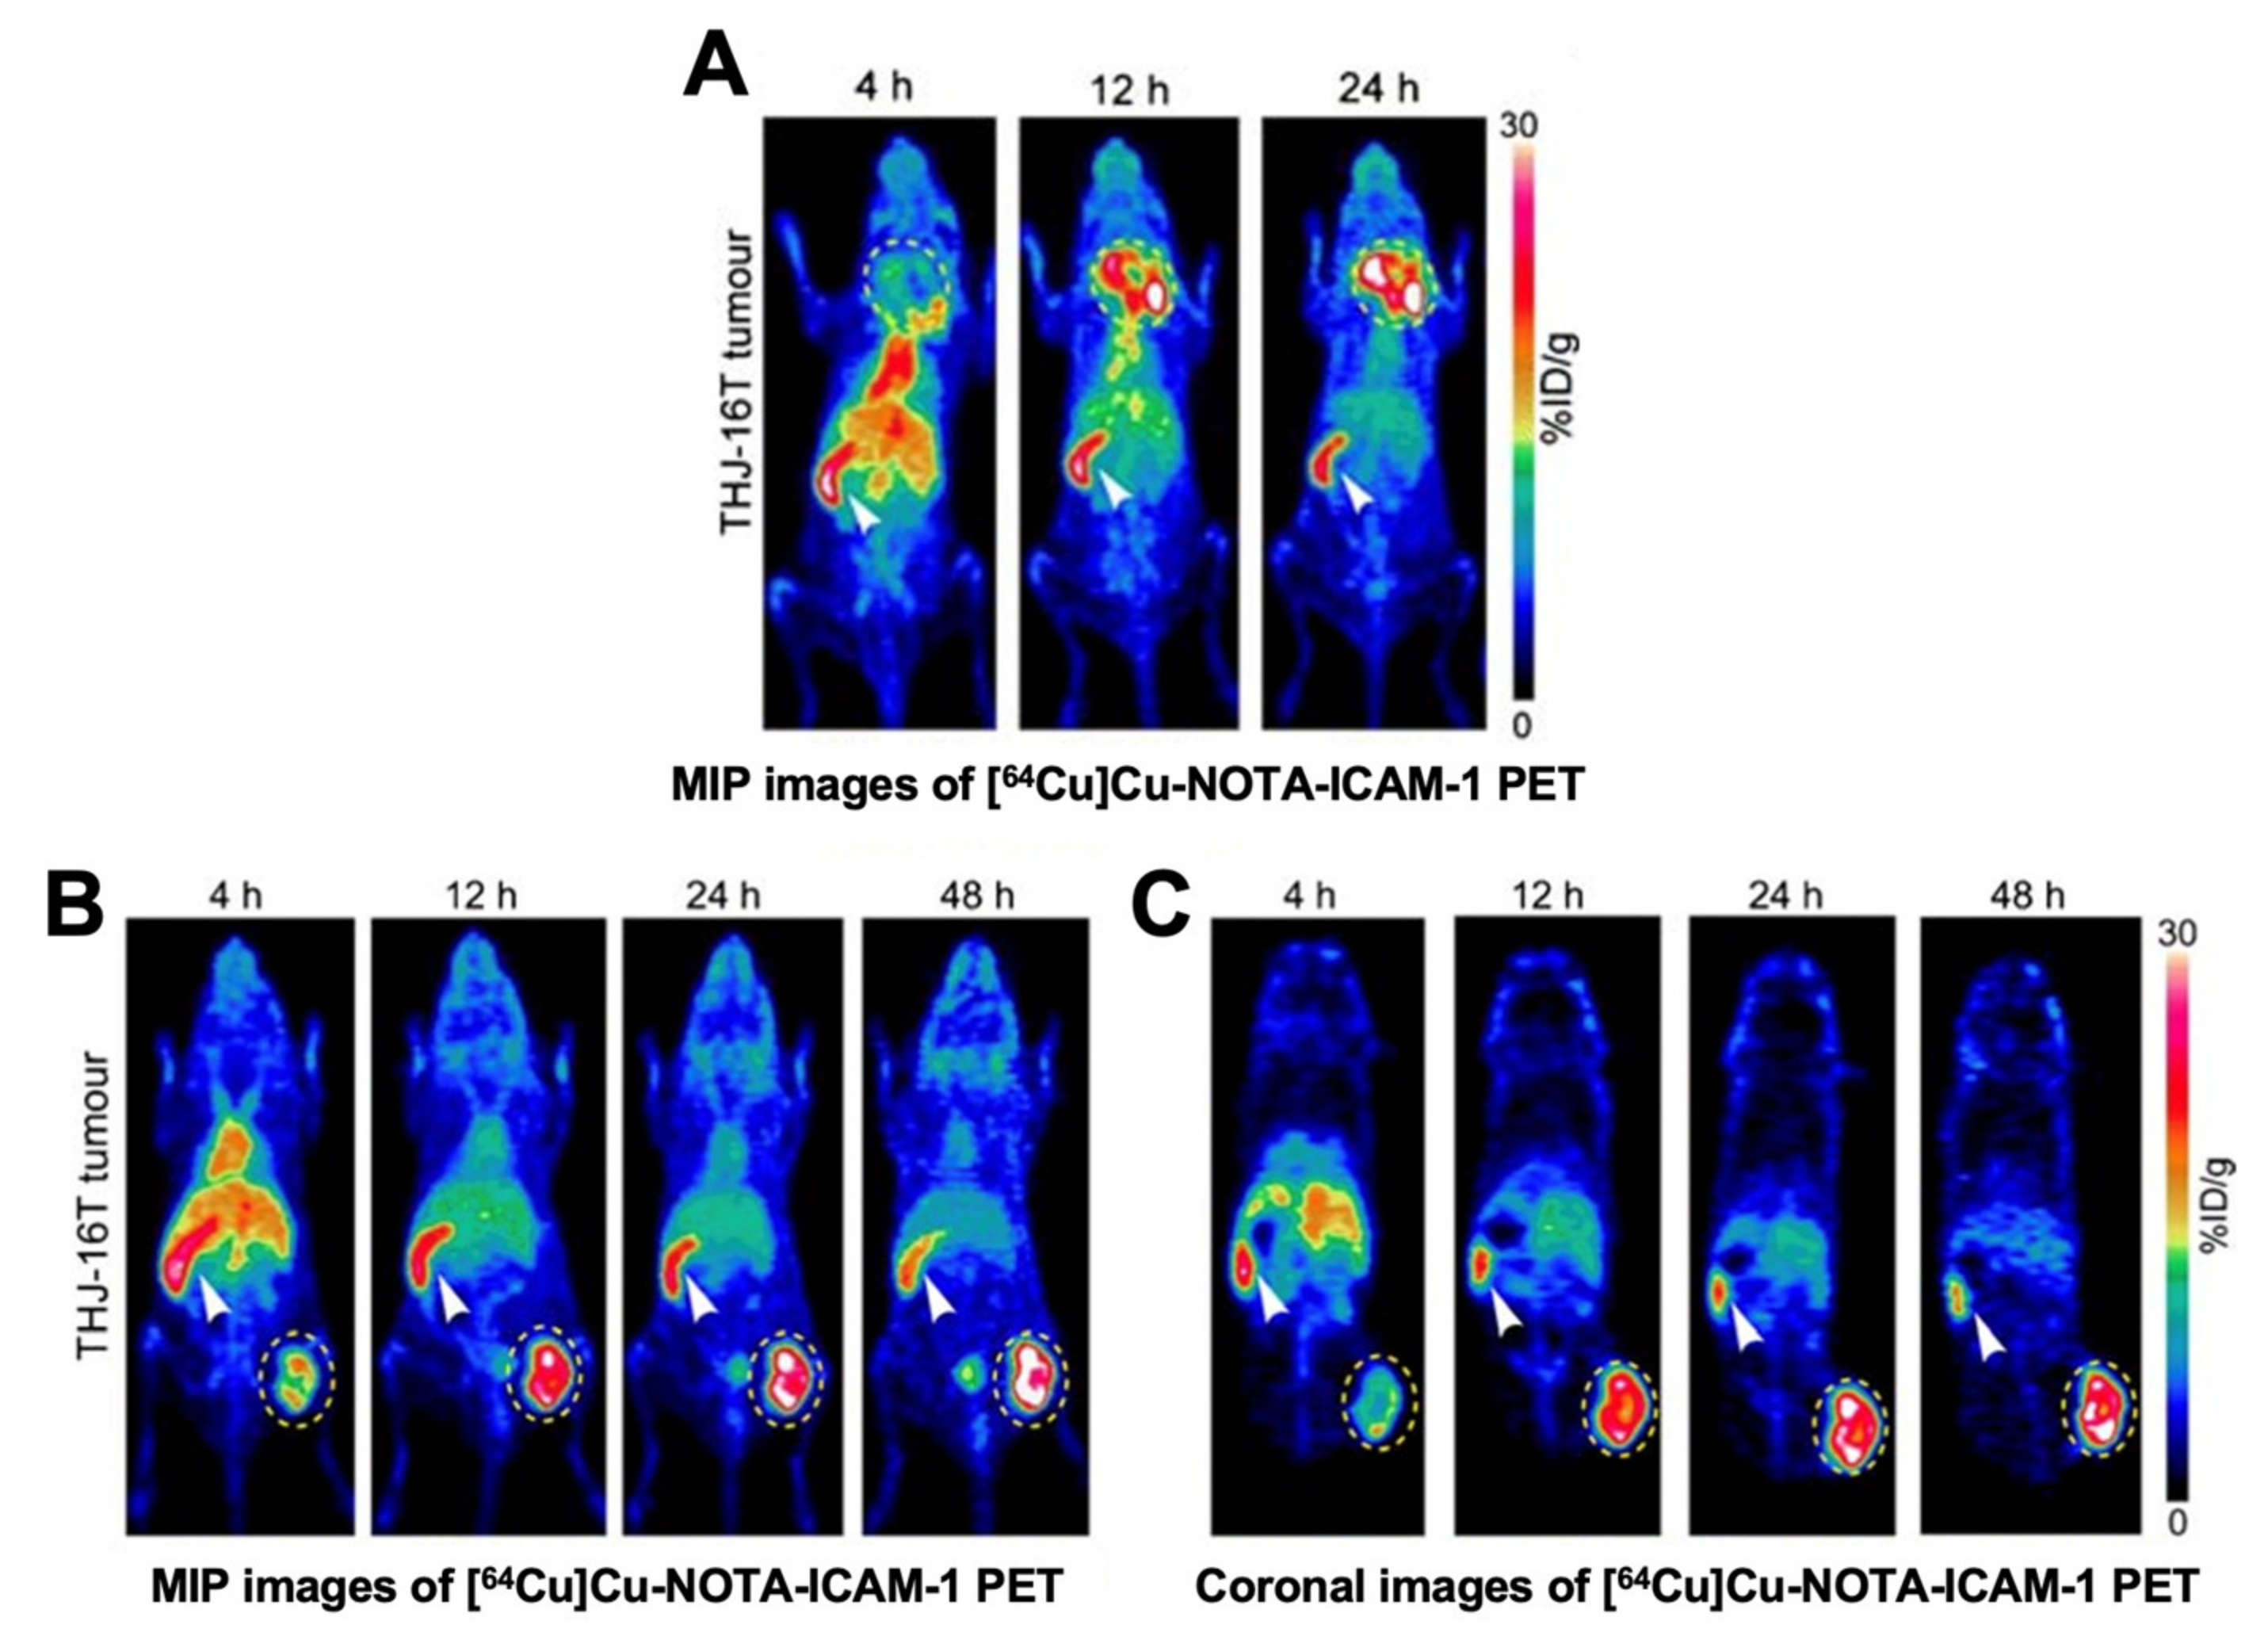

- Wei, W.; Jiang, D.; Lee, H.J.; Li, M.; Kutyreff, C.J.; Engle, J.W.; Liu, J.; Cai, W. Development and Characterization of CD54-Targeted ImmunoPET Imaging in Solid Tumors. Eur. J. Nucl. Med. Mol. Imaging 2020, 47, 2765–2775. [Google Scholar] [CrossRef]